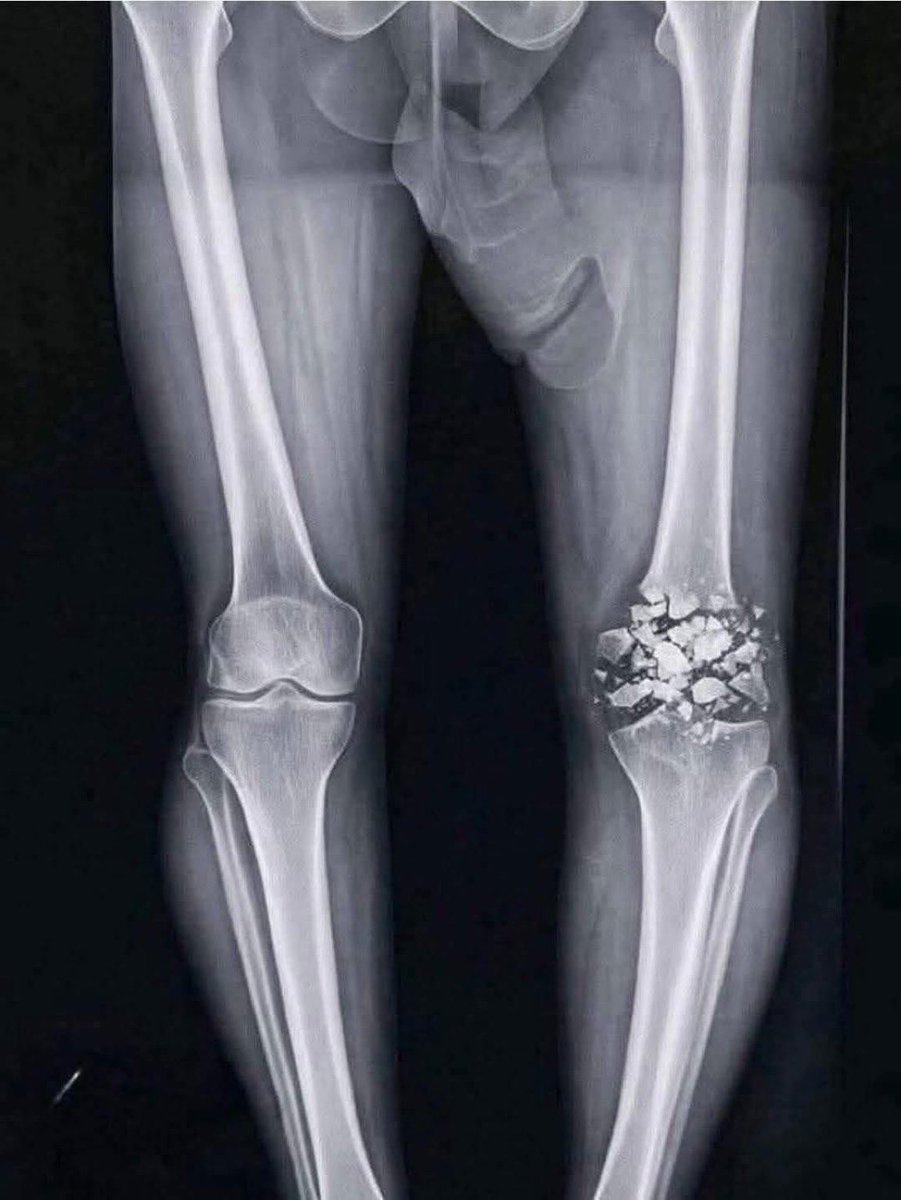

Mbappé ni forzó para un récord ni se borra de partidos importantes. Mbappé lleva tiempo con dolor en la rodilla pero los médicos le decían que todo estaba bien, por lo que el siguió forzando. Ya ha salido a la luz que la resonancia era de la rodilla equivocada. @RMCsport